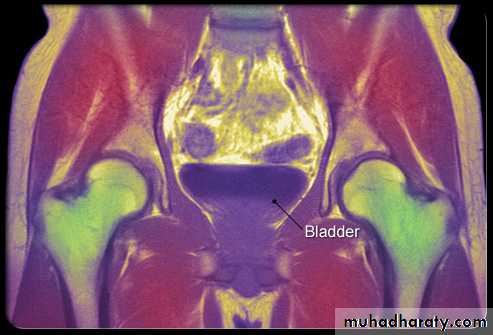

Bladder:

Is situated behind the symphysis pubis and is covered superiorly and anteriorly by peritoneum.

MRI